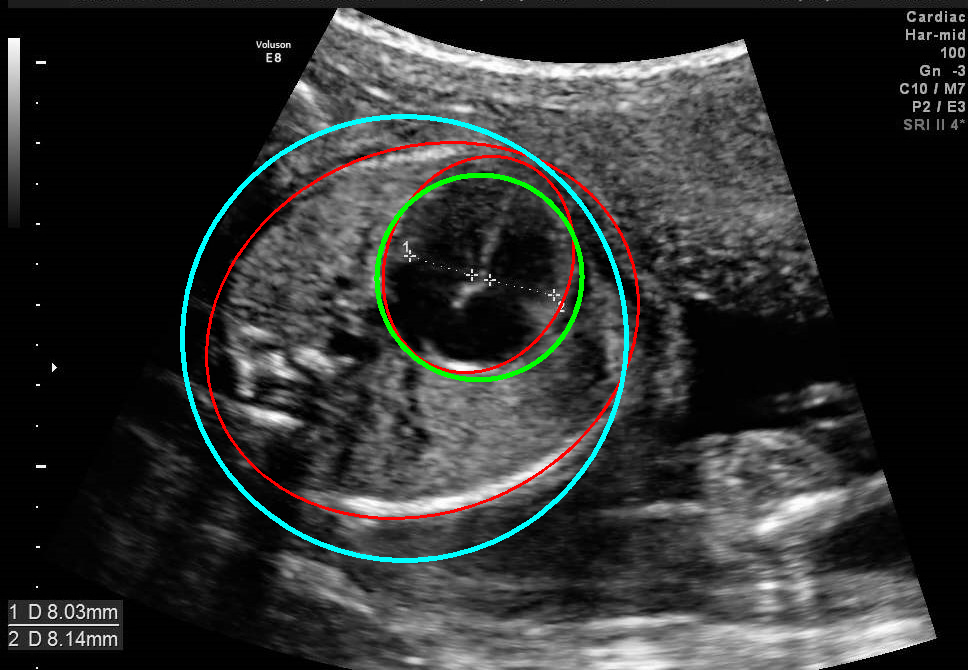

Visualization results of different methods.

Although the segmentation model trained on the fetal ultrasound dataset achieves a relative high average dice scores averaging over 0.9, the fitted ellipse highly depends on the segmentation results. As shown in the middle row of Fig. 2, the segment-based ellipse-fit method performs well when the image quality is good (first row), but the performance degrades when the segmentation is affected by image artifacts such as the acoustic shadowing (second and third row). Our proposed method is more robust to image quality and shadows. We also tried to compare to the GPN [9] with their open source code on our dataset, however, the results are not comparable to ours and those presented in Table. 1. It is difficult to conclude whether it is caused by the network itself or the training strategies. We, therefore, did not include the comparative results in this work.

As shown in Fig. 3 , both the proposed ellipse regression loss and IoU loss are necessary for ellipse detection. If the EllipseNet only supervised by IoU loss (first column), the model fails to optimize the major and minor axis separately, and the predicted ellipses degenerate into circles like the CircleNet. It is clear that the supervision of IoU loss can help to improve the prediction of location and shape (first and second row) and to correct the angle (last row).